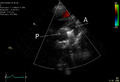

PDA is usually diagnosed using noninvasive techniques. Echocardiography (in which sound waves are used to capture the motion of the heart) and associated Doppler studies are the primary methods of detecting PDA. Electrocardiography (ECG), in which electrodes are used to record the electrical activity of the heart, is not particularly helpful as no specific rhythms or ECG patterns can be used to detect PDA.[3]